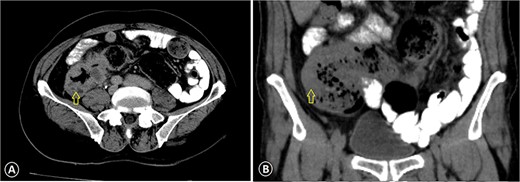

A 68-year-old male patient, an ex-smoker with no significant family history of malignancy, has a known case of leukemia treated since 2018 and was diagnosed with colon cancer (pT3N1M0) in April 2023. A colonoscopy was done at the time and showed a fungating mass in the ascending colon causing significant luminal narrowing. The preoperative carcinoembryonic antigen (CEA) level was 15.3 (normal <5.0 ng/ml), and CA19-9 was 343 (normal range 0–37 units per milliliter). Multiple biopsies were taken, which confirmed invasive, moderately to poorly differentiated adenocarcinoma. A CT scan identified the mass in the ascending colon without evidence of distant metastasis (Fig. 1). The patient underwent a right hemicolectomy. Histopathological analysis of the tumor revealed invasive, moderately to poorly differentiated adenocarcinoma with focal neuroendocrine differentiation, measuring 9 cm in greatest dimension, invading the muscularis propria and peri-intestinal fat, and exhibiting numerous lymph vascular invasions with clear margins. Two out of twenty lymph nodes were positive for malignancy. Molecular profiling indicated wild-type KRAS and BRAF, deficient MMR, and negative HER-2. The tumor cells were positive for CDX2 while negative for synaptophysin. The postoperative (CEA) level was 6 ng/ml.

Ascending colon cancer. The CT image with IV contrast revealed a markedly thickened colonic wall (arrow) with pericolonic inflammation: (A) axial view CT scan and (B) coronal view CT scan.